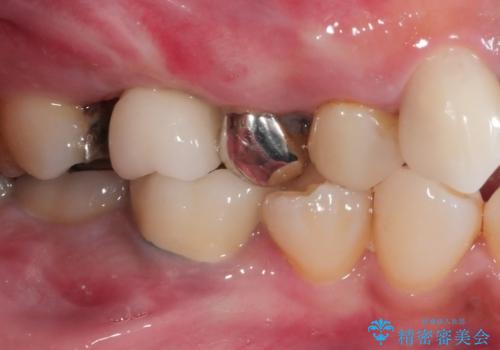

インプラント治療により問題無く奥歯で噛めるようになりましたが、奥歯の噛み合わせが強いためインプラント周囲の骨吸収や他の歯の破折等が起きる可能性があります。

夜間就寝時のマウスピース装着、定期的なメンテナンスでレントゲン、噛み合わせの確認は必須です。